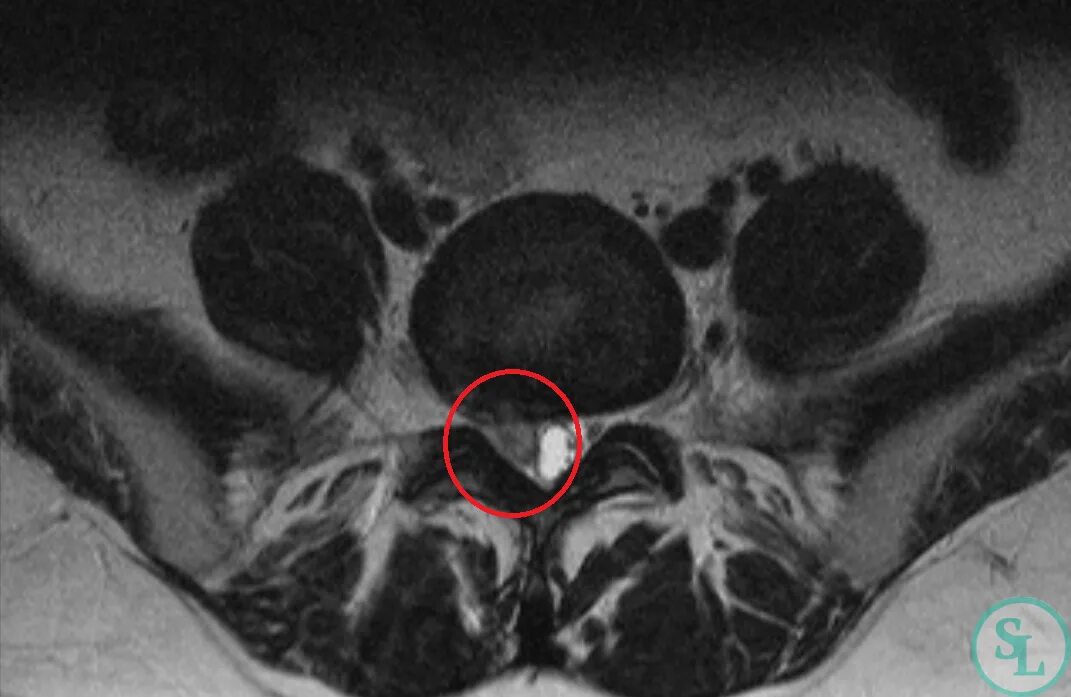

Задняя протрузия диска l5